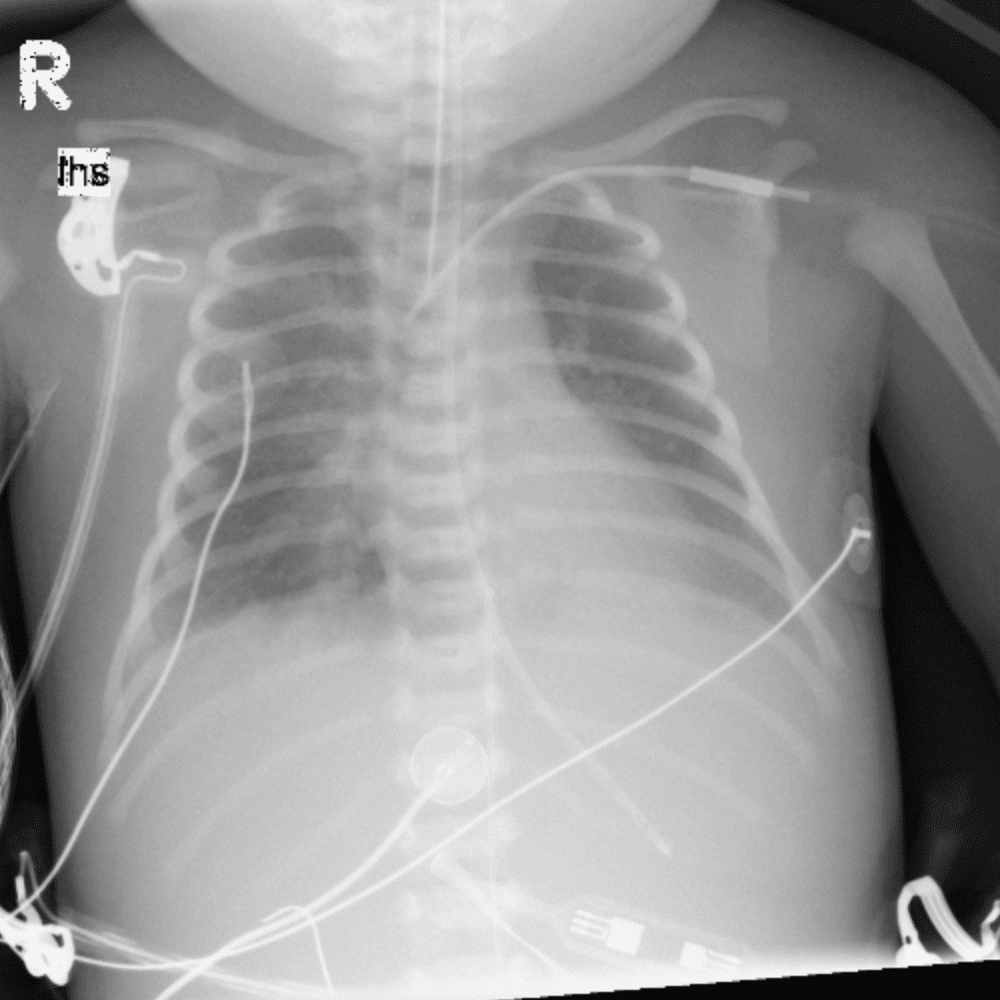

Peds Chest

Practice

Simulates call by including subtle or difficult cases and some normals.

50 cases